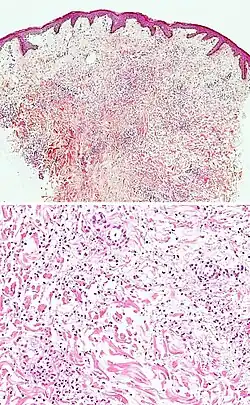

| Lichen sclerosus | Hyperkeratosis, atrophic epidermis, sclerosis of dermis and dermal lymphocytes.[7] | ![]() | ||

Neutrophilic infiltrate

| Main conditions[2] | Characteristics | Micrograph | Photograph |

|---|---|---|---|

| Urticaria, neutrophil predominant | ![]() |

![]() | |

| Dermatitis herpetiformis |

|

![]() |